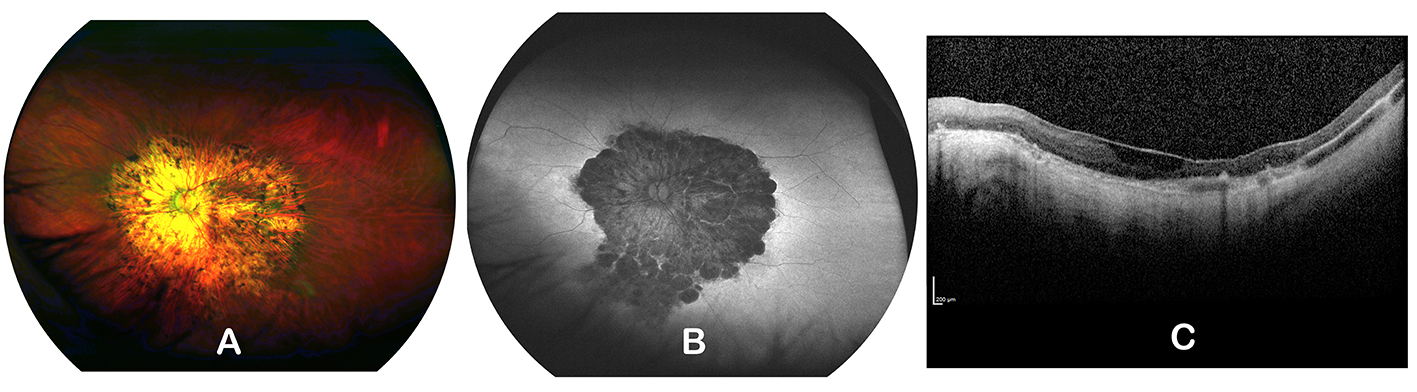

Figure 2. Retinal imaging for subject P2 (A–C). (A) Fundus imaging in P2 demonstrated widespread posterior pole chorioretinal atrophy surrounded by a rim of hyperautofluorescence

(B). (C) SD–OCT imaging revealed widespread retinal atrophy (size bar=200 μm).